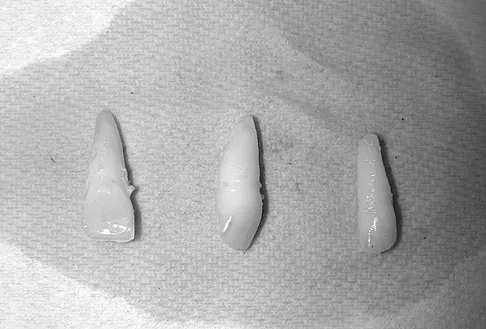

Question 75

A 15-year-old female field hockey player sustains a blow to the mouth from a hockey stick. Three front teeth are knocked out and shown in Figure 4. In addition to calling a dentist immediately, what is the next best step in management?